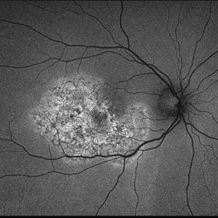

Optos ultra wide field auto fluorescent image of 20-year-old female presenting with serpiginous choroidal atrophy. Patient was unaware of vision loss OD, until accidentally covering OS and noticing the change. Acuity of 20/200 OD and 20/15 OS at time of imaging.

Photographer: Jessica Norkus

Imaging device: Optos Ultra Wide Field Camera

Condition/keywords: fundus autofluorescence (FAF), fundus photograph, macula lesion, macula serpiginous choroidopathy, Optos, ultra-wide field imaging